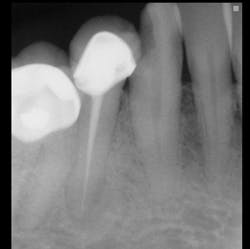

The following images show a patient with limited finances but a strong desire to retain her teeth. The crowns present in the quadrant placed by a previous dentist show that the patient at one time had adequate finances for crowns.

The technique for building up restorations to restore deep carious lesions follows: